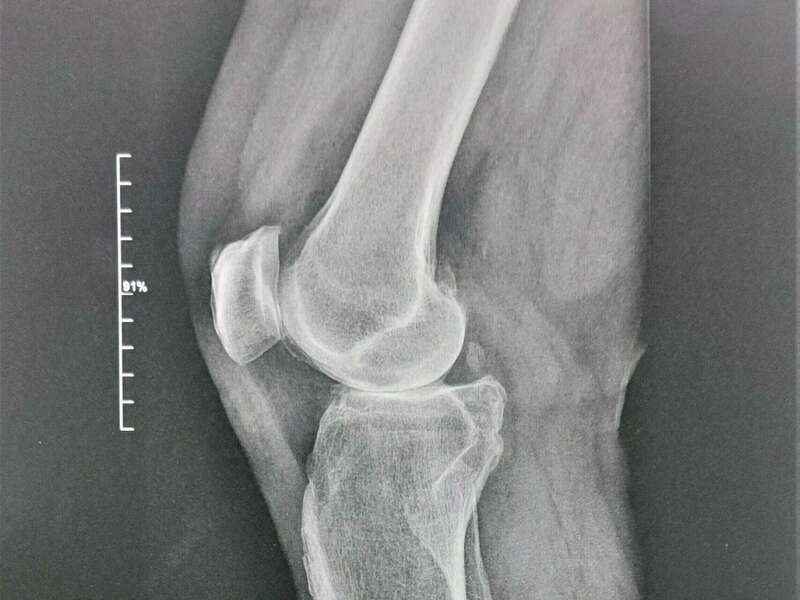

L’articulation du genou assure la jonction entre le fémur (condyles fémoraux), le plateau tibial et la rotule (patella). Elle se compose de deux articulations : l’articulation fémoro-patellaire entre le fémur et la rotule et l’articulation fémoro-tibiale qui elle-même se divise en deux compartiments (interne et externe).

L’ensemble des zones de frottement entre les différents os est recouvert d’un cartilage d’une épaisseur d’environ 3 à 4 mm d’épaisseur qui facilite le glissement entre les différentes surfaces articulaires.

La stabilité de cette articulation est obtenue par de nombreuses structures anatomiques. Les ménisques sont des fibrocartilages qui augmentent la congruence articulaire et ont un rôle chondroprotecteur majeur. Les ligaments croisés antérieurs et postérieurs contrôlent la translation tibiale antérieure et postérieure et limitent la rotation tibiale. La membrane synoviale permet de lubrifier l’articulation en sécrétant le liquide synovial. De nombreux autres éléments ligamentaires, capsulaires, et musculaires sont aussi impliqués dans la stabilité du genou.

Des excroissances osseuses, appelées ostéophytes, des kystes osseux et des ulcérations cartilagineuses se forment progressivement. En réponse, la membrane synoviale devient inflammatoire et produit un liquide synovial. L’excès de pression articulaire et l’inflammation sont les causent des douleurs de genou. La perte de congruence de l’articulation entraîne quant à elle, une diminution de la mobilité articulaire.

- Les déformations d’axe : genu varum (jambes arquées) et genu valgum (jambe en X)

- Les anomalies anatomiques plus ou moins constitutionnelles : inégalité de longueur de membre, dysplasie fémorotibiale, les antécédents de fracture du genou, les lésions ligamentaires.